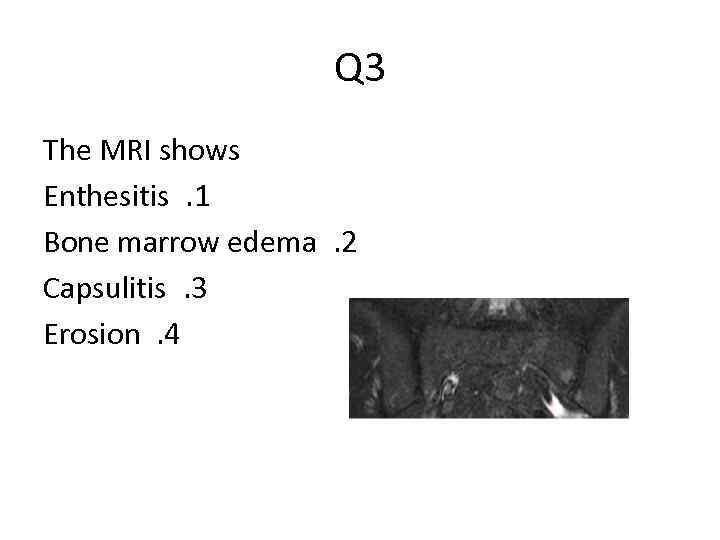

Q 3 The MRI shows Enthesitis. 1 Bone marrow edema. 2 Capsulitis. 3 Erosion. 4